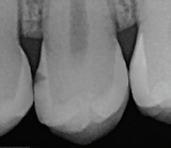

In the endodontic stage, conservative endodontic preparation and obturation with modern techniques are performed as they are for any tooth. All endodontic procedures are performed under an operating microscope to maximize visualization and illumination of the fracture line (Fig 1). The coronal portion of the newly placed gutta percha is removed 2 to 3 mm below the deepest extent of the crack in the affected canal to prepare for intraradicular barrier placement (Fig 2). Gutta percha is also removed 2 to 3 mm into the other noncracked canal orifices in the tooth to prepare for traditional orifice barriers. Microscopic transillumination with a fiber-optic light, in which an LED light probe is placed against buccal or lingual tissues overlying the roots, is utilized to illuminate the root and enhance visualization of the crack (Fig 3). A flowable resin-modified glassionomer or composite resin is then placed in this newly created void from the level of the gutta percha to the floor of the pulp chamber in all canal orifices (Fig 4). A composite resin core is then placed to permanently restore the endodontic access. If a temporary or permanent crown is not placed immediately after the endodontic procedures, the tooth is reduced

Periapical radiograph at the completion of the endodontic protocol. Resin-modified glass ionomer cement is placed as an intraradicular barrier in the distal canal, along the pulpal floor, and as an orifice barrier in the mesial canals.

Fig 1. Microscopic visualization of the radicular extension of the crack (arrows) entering the canal.

Fig 4.

Fig 3. Microscopic transillumination. A. Canal space viewed under microscopy without transillumination. B, C. Same canal viewed at different angles with the aid of a fiber-optic light. Transillumination reveals a root fracture.

Fig 2. Gutta percha removed 2 mm apical to the terminus of the fracture (arrows).